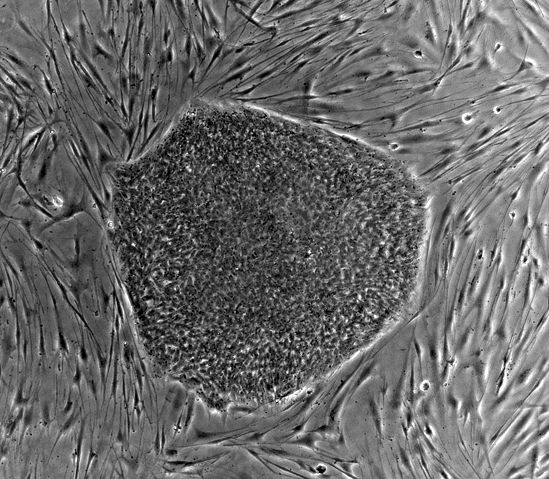

This image is of cell line SA02 ( http://stemcells.nih.gov/research/registry/cellartis.asp). Image is of human embryonic stem (hES) cell colony on a mouse embryonic fibroblast (MEF) feeder layer.

| current | 18:43, 12 July 2007 | 1,024×894 (255 KB) | Id711 ( Talk | contribs) | (For upload to Stem Cells and possibly Embryonic Stem cells. This image is of cell line SA02 (http://stemcells.nih.gov/research/registry/cellartis.asp). Image is of human embryonic stem (hES) cell colony on a mouse embryonic fibroblast (MEF) feed) |